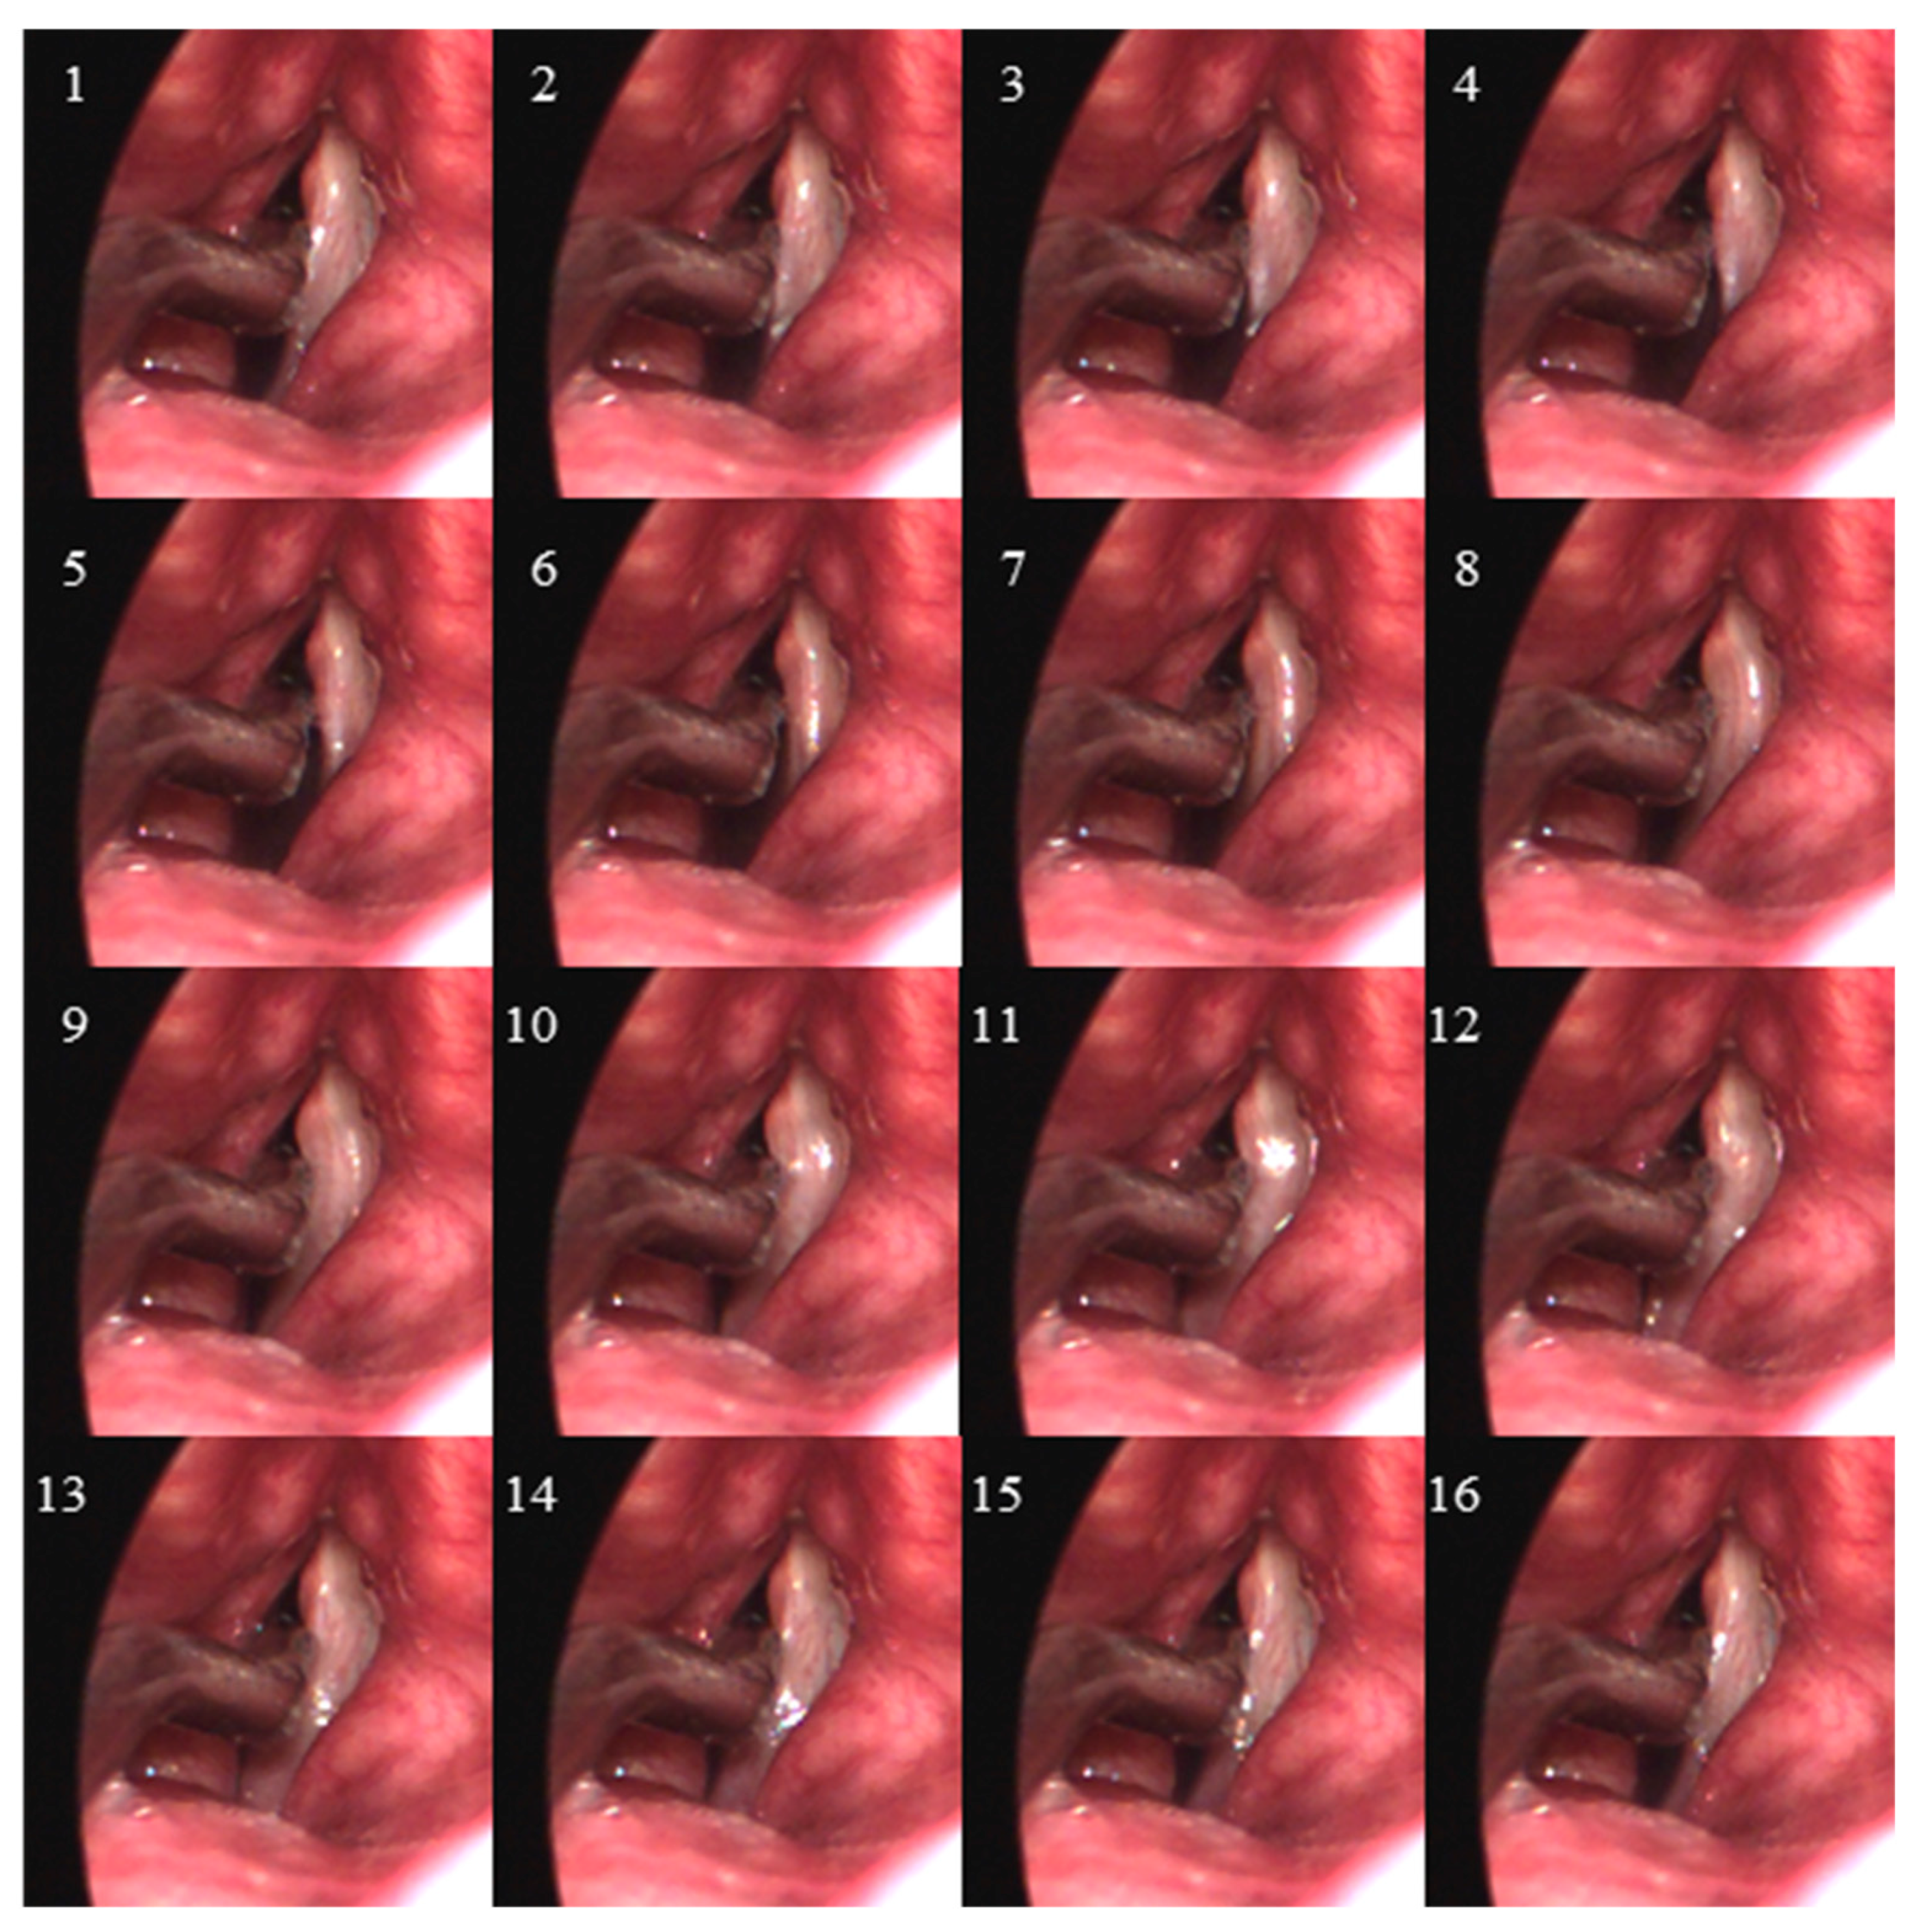

- Endoscopic visualization is necessary to guide placement of the ISP probe such that the distal pressure sensor at the probe tip is positioned subglottally and the proximal sensor is positioned in the glottis in the phonatory strike zone to sense vocal fold impact collision pressure during phonation.

- In individuals with a hemilaryngectomy, the ISP probe should rest on the medialized scar band that replaces the excised vocal fold tissue, such that the pressure-sensing element comes into direct contact with the functioning vocal fold.

- The positioning of the intraglottal pressure sensor is in the phonatory strike zone if the following waveform characteristics are exhibited:

- An impulsive peak in the direction of increasing pressure at the instant of vocal fold contact;

- A more rounded peak following the impulsive peak that senses aerodynamic pressure build-up during the open phase; and

- A minimum value approaching zero or negative pressure immediately preceding the impulsive peak of the subsequent phonatory cycle, reflecting rapidly decreasing intraglottal pressure as airflow accelerates.